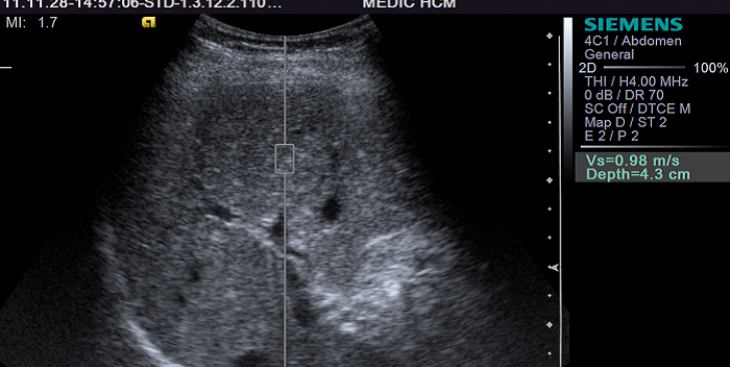

Buồng trứng phải có nang khi mang thai có nguy hiểm không?

Trong thời kỳ mang thai nếu phát hiện buồng trứng phải có nang sẽ ảnh hưởng rất lớn đến tâm lý của những bà bầu. Thế nhưng, buồng trứng phải có nang khi mang thai có nguy hiểm không? Bài viết hôm...